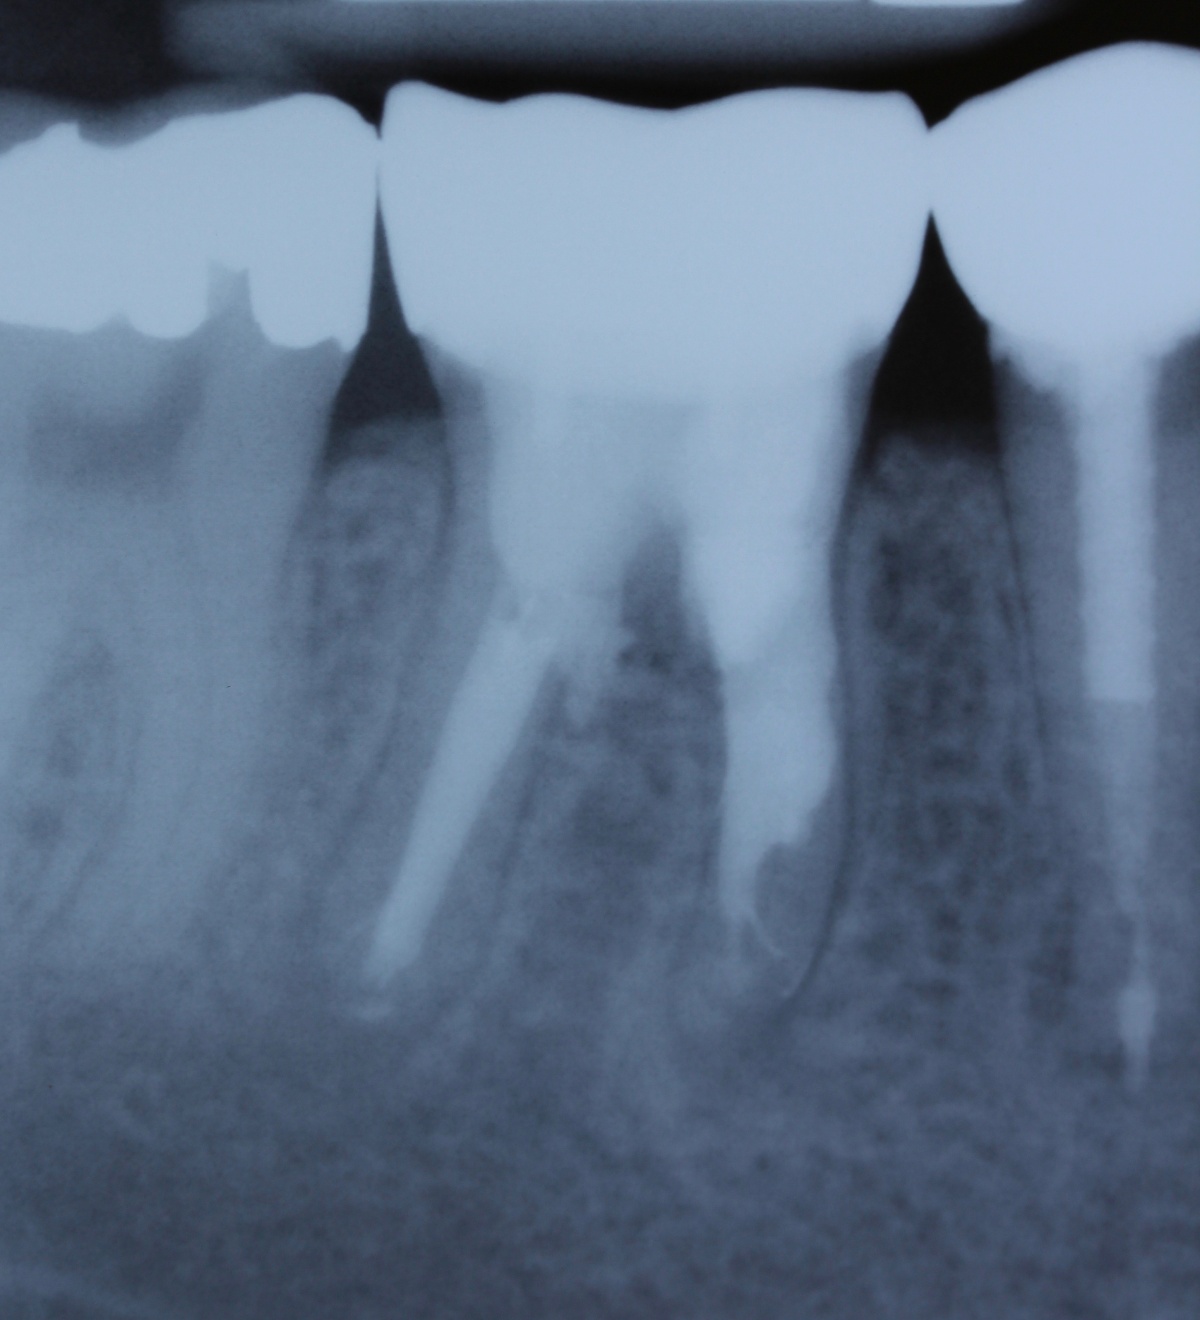

Idealerweise können mit den Maßnahmen der regenerativen Parodontalchirurgie durch Entzündungen verloren gegangenen Anteile des Parodontiums wiederhergestellt werden. Dazu stehen verschiedene Operationsverfahren zur Verfügung. Einen wissenschaftlich belegten Behandlungserfolg bieten insbesondere Maßnahmen der gesteuerten Geweberegeneration (GTR, Guided Tissue Regeneration) und die Anwendung von Schmelzmatrixproteinen. Da ein Erfolg dieser Maßnahmen ganz maßgeblich von der Defektmorphologie abhängig ist, gilt es eine strenge Indikationsstellung zu beachten. Als prognostisch günstig gelten dreiwandige vertikale Knochendefekte sowie Furkationsdefekte des Grades 2 bei Unterkiefermolaren. Bei der Anwendung der gesteuerten Geweberegeneration können verschiedene Barrieremembranen zum Einsatz kommen. Diese verhindern im Idealfall eine Besiedlung des Defekts mit den schnell proliferierenden Zellen des Epihels oder Bindegewebes und ermöglichen so eine Regeneration mit der Neuausbildung parodontalen Attachments. Eine Therapie mit gesteuerter Geweberegeneration ist technisch durchaus anspruchsvoll und sollte daher nur von parodontalchirurgisch geübten Operateuren angewendet werden. Der Erfolg einer solchen Maßnahme ist in den Abb. 7 und 8 dargestellt. Mittels einer ePTFE-Membran konnte der mesiale vertikale Defekt zur Ausheilung gebracht werden und zeigte sich auch nach fünf Jahren stabil. Vergleichbar gute Erfolgsraten können auch mit der Anwendung von Schmelzmatrixproteinen erzielt werden. Hier sei beispielhaft auf die Studie von Sanz und Mitarbeitern aus dem Jahre 2004 verwiesen, wo mit einem Schmelzmatrixprotein ähnlich gute Ergebnisse hinsichtlich dem Attachmentgewinn und der Reduzierung der Sondiertiefen wie mit Membranen erzielt werden konnte. Als vorteilhaft gegenüber Membranen hat sich die signifikant geringere Rate von Komplikationen gezeigt, zudem ist die Anwendung von Schmelzmatrixproteinen technisch deutlich einfacher.